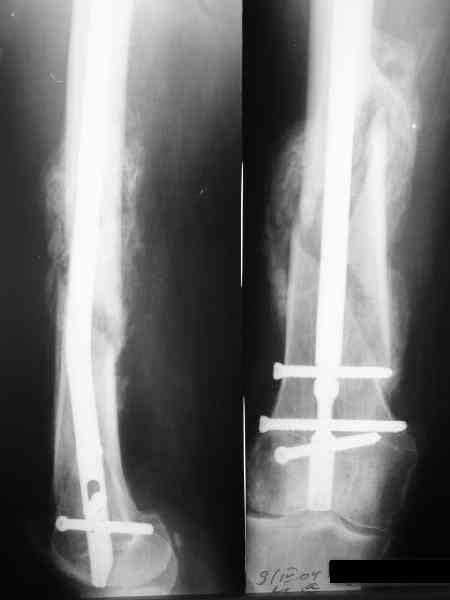

Пациенту М., 30-ти лет, 1,5 года назад в одной из московских больниц был выполнен остеосинтез бедренной кости штифтом UFN (диаметр штифта 9 мм).

К нам больной поступил с признаками ложного сустава бедренной кости, перелома

штифта и дистального блокирующего винта (images 1,2,3).

27 марта выполнено удаление блокирующих винтов (сломанный винт пришлось высверливать цапфен-бором), сломанного штифта (дистальный фрагмент удален через канал, образованный разверткой из коленного сустава - image 4),

рассверливание костно-мозгового канала, реостеосинтез штифтом UFN (при проведении штифта в дистальном отломке мы использовали поляризующий винт, диаметр штифта 10 мм). После операции в связи гемартрозом дважды (на 1 и 3 сутки) выполняли пункцию коленного сустава. Сейчас признаков скопления жидкости в полости сустава нет. Послеоперационные рентгенограммы - images 5, 6, 7.